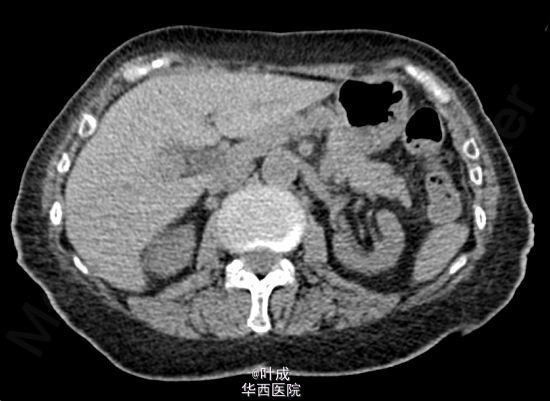

患者女,80岁,因“腹胀、呕吐1-天”入院。呕吐10+次,伴背痛。既往发现血压升高10年,最高180/100mmHg,药物控制一般;发现血肌酐升高3年,目前行规律血液透析(biw)。入院查体T:36.5oC,P:85次/分,R:22次/分,BP:186/76mmHg。神志清楚,心界向左扩大,心律齐。双肺呼吸音粗,散在湿罗音。全腹软,无明显压痛及反跳痛,腹部未触及包块。双下肢轻度水肿。辅助检查:血常规:Hb 109 g/L,WBC 12.51 10^9/L,N 10.65 10^9/L;血生化:ALT 61 IU/L,AST 239 IU/L,肌酐 585.0 umol/L,淀粉酶 428 IU/L,脂肪酶 998 IU/L,胆红素、电解质未见异常;心肌标志物示:肌钙蛋白-T 82.1 ng/L,尿钠素 >35000 pg/ml。CT示:胆囊炎,胰腺形态改变,胰周渗出,双肺散在条索、斑片、磨玻璃影及实变影,双侧胸膜增厚,双侧胸腔少量积液,心脏长大,心包少量积液(图1-2)。 入院诊断:1、急性胰腺炎(中度 原因?) 2、高血压病III级 极高危组 心脏长大 3、慢性肾功能不全(尿毒症期) 4、肺部感染 5、胆囊炎。 患者入院时一般情况可,于当日夜间感心累、气紧,拒绝面罩吸氧,后突发呼吸、心跳骤停,立即行胸外心脏按压,予血管活性药物及呼吸兴奋剂,请麻醉科会诊行气管插管有创呼吸机辅助通气,予镇静、镇痛、控制血压、纠正酸碱失衡等对症处理。患者恢复窦性心律,镇静下有创呼吸机人机配合可。反复沟通后,患者家属拒绝转ICU并签字。住院期间患者无尿,检测血气分析示氧合可,代谢性酸中毒逐步加重,血钾、血钠、血肌酐逐渐升高,住院第14天家属签字拔除气管插管,40分钟后患者临床死亡。部分实验室检查结果见下图。